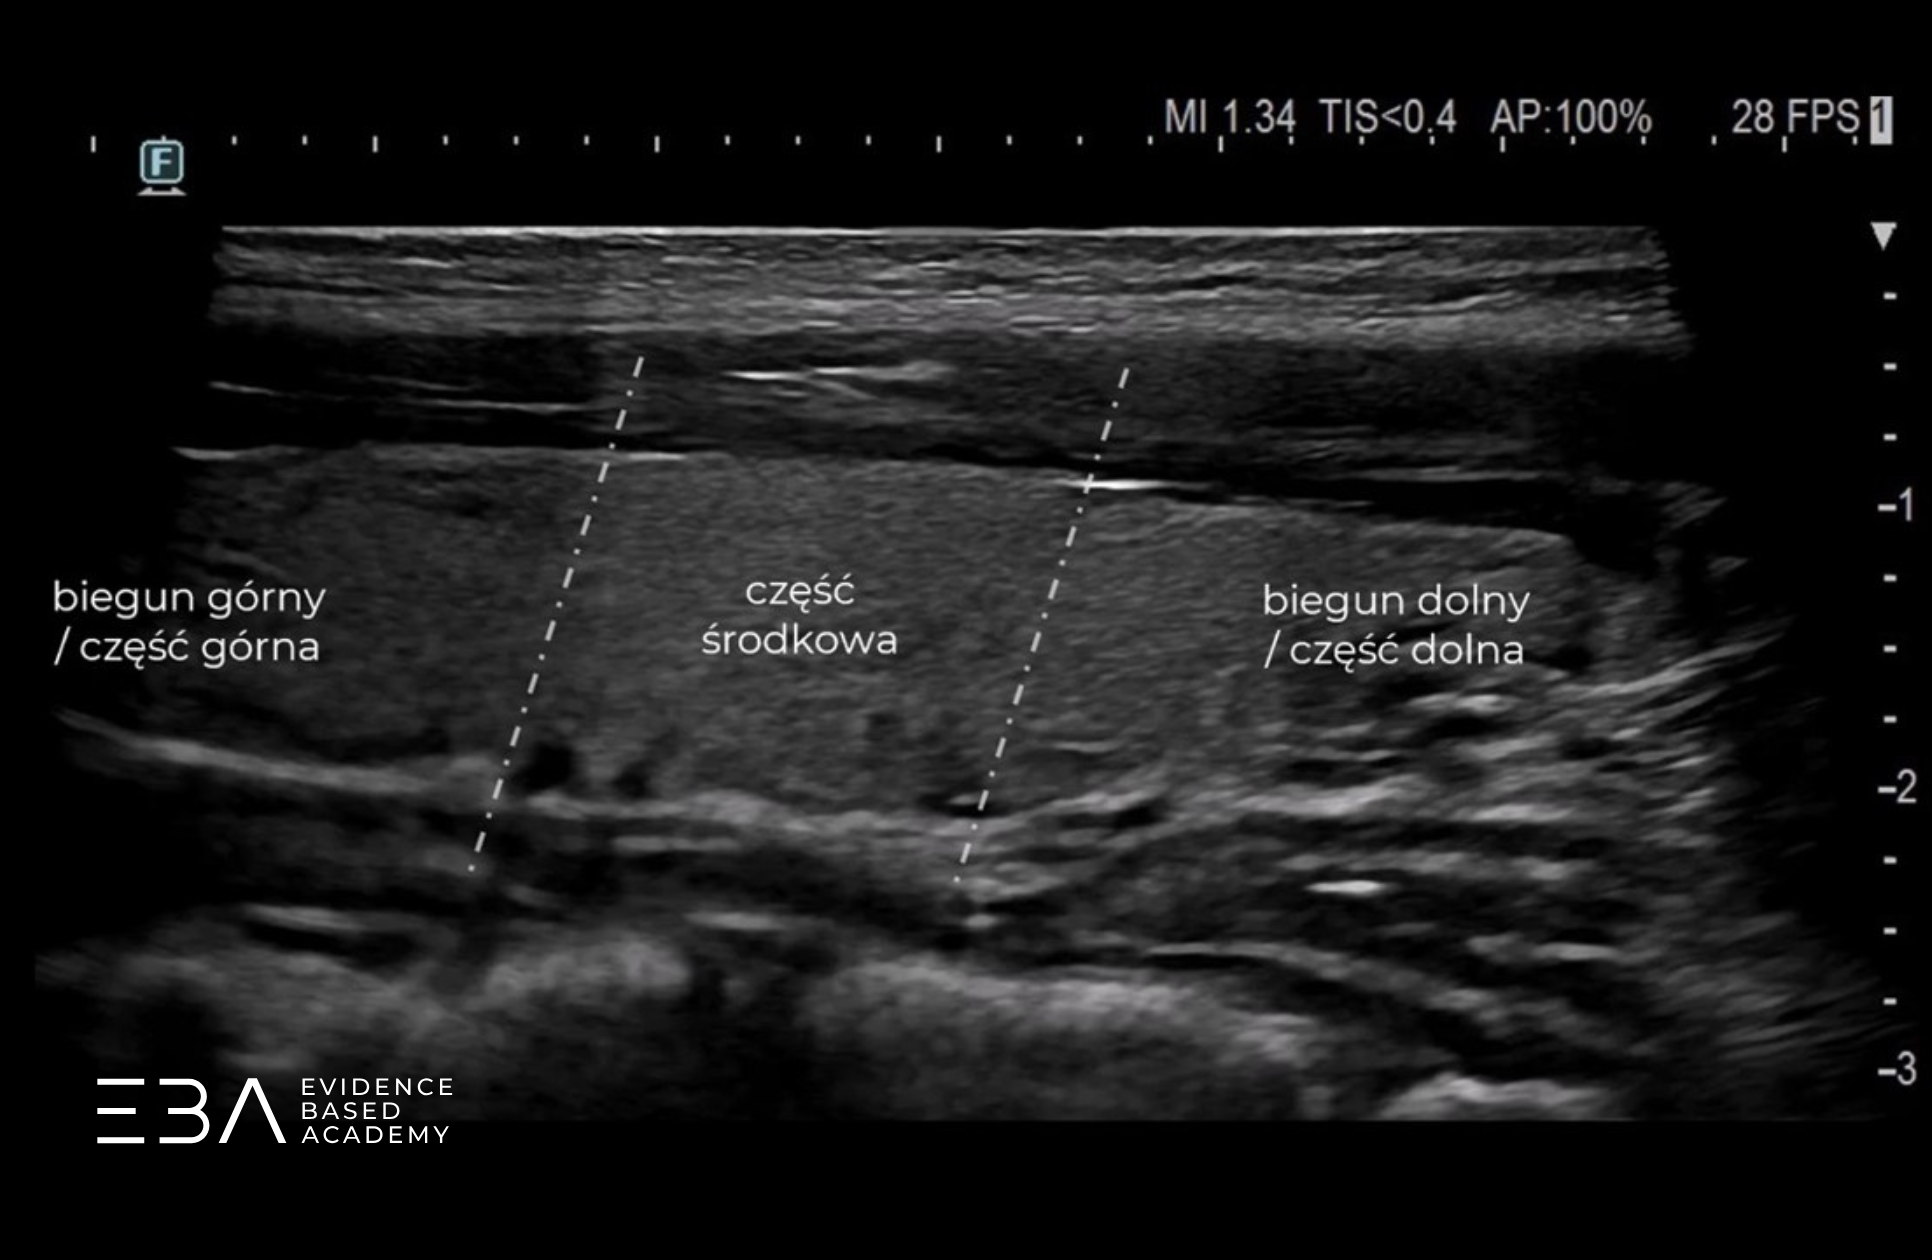

W projekcji podłużnej możemy podzielić płat na trzy części. Po lewej stronie obrazu (po stronie znacznika) widoczna jest część górna (inaczej biegun górny), na środku – część środkowa, a po prawej stronie obrazu – część dolna (inaczej biegun dolny).

Projekcja podłużna z podpisami części płata.

Uzyskując przekrój podłużny przez płat, wybieramy miejsce, w którym płat jest najdłuższy. Po zatrzymaniu obrazu umieszczamy kursor w najdalej położonym punkcie górnego bieguna i wyznaczamy linię do najdalej położonego punktu bieguna dolnego, zgodnie z osią długą płata.

Pomiar długości płata głowicą liniową.